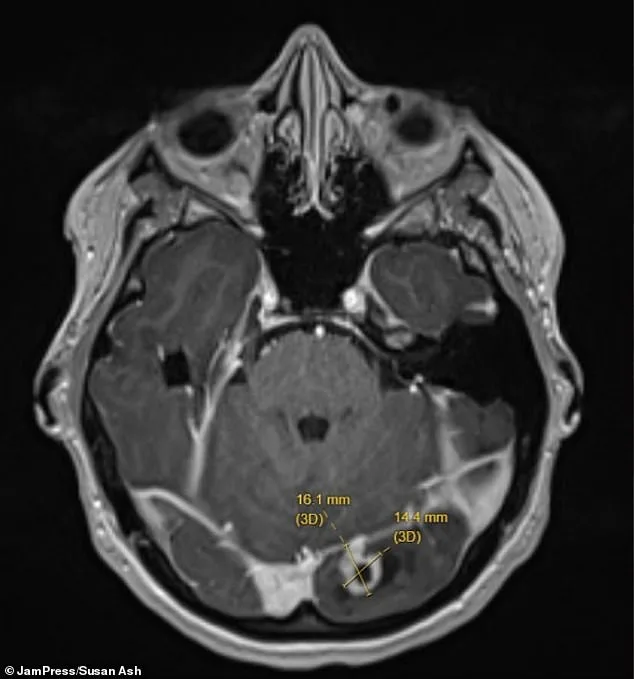

The picture of the scan shows the tumor shown by the yellow lines on her left occipital lobe — the part of the brain at the back of the head responsible for processing visual information from the right eye.

Fortunately, the mass was not cancerous, but its location explained the strange flashes Ms Ash had been experiencing.

She was rushed to hospital, where imaging scans revealed a marble-sized tumor pressing on her brain.

A hospital scan revealed the existence of a brain tumor, bringing with it a life-altering decision: to leave the tumor or undergo surgery that could potentially save her life but risk losing vision in her right eye.